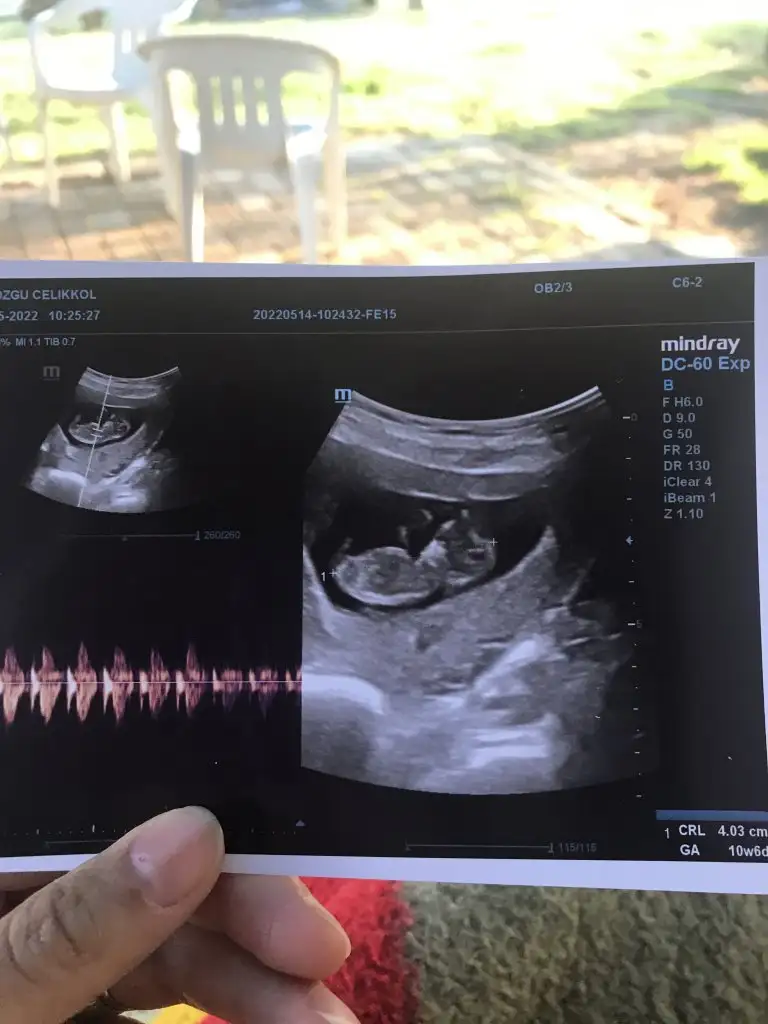

Bugün ki son resimlerimiz canım üçhagta sonra söyleyecekmiş doktorumuz